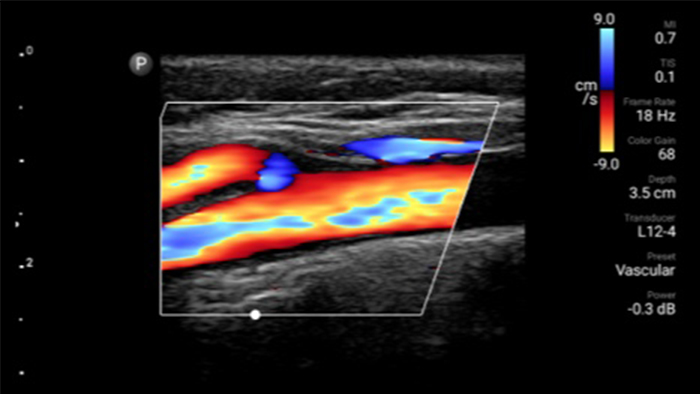

Ultrasound exams can improve your ability to identify and successfully treat skin abscesses.

Lumify L12-4 broadband linear array transducer

POC ultrasound for soft tissue